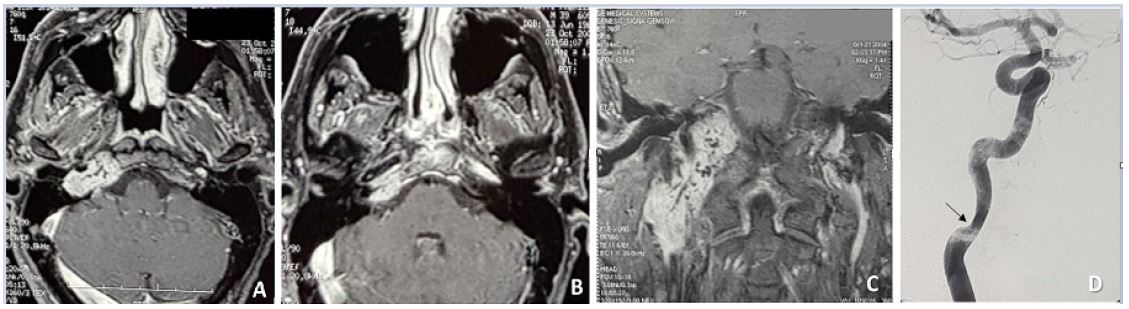

High-Resolution Computed Tomography (HRCT) of the temporal bone and skull base and gadolinium-enhanced Magnetic-Resonance Imaging (MRI) of the brain and neck showed involvement of the vertical and horizontal portions of the petrous segment of the ICA and two distinct masses at the level of the parapharyngeal space and jugular foramen, suggestive for a TJP (Class C3De1) and VP (Stage I) (Figure 1).

Angiography showed occlusion of the left common carotid artery and ICA. The distal cervical segment and the vertical portion of the petrous segment of the right ICA were irregular and stenotic due to tumor encasement (Figure 1). The patient underwent stenting of the right ICA and received antiplatelet therapy starting 1 week before the procedure. Seven weeks after stenting, the patient underwent embolization of the right ascending pharyngeal and occipital arteries. Two days later he was operated through a right infratemporal fossa type a approach and total removal was achieved with no complications. Right FN function improved from grade VI House-Brackmann scale in the early post-operative period to grade III two years after surgery. The right vocal cord palsy was well tolerated thanks to the contralateral compensation with no need for pharyngolaryngeal surgery. Doppler ultrasound at discharge and at 6, 18 and 36 months after surgery showed a patent right ICA. The patient underwent yearly HRCT and MRI scans for the first 5 years and approximately every 2 years for the subsequent period.

Figure 1: (A,B,C,D): C3De1 TJP (A,B), C3De1 TJP and VP stage I (C) on Gd-enhanced MRI scans. Stenosis of the distal cervical C1 segment of ICA (arrow) can be appreciated on angiography (D).